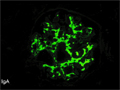

- ★(4)IgA nephropathy

Microscopic findings (HE, high power view): Slight expansion of the mesangium is noted (area within red dotted line).